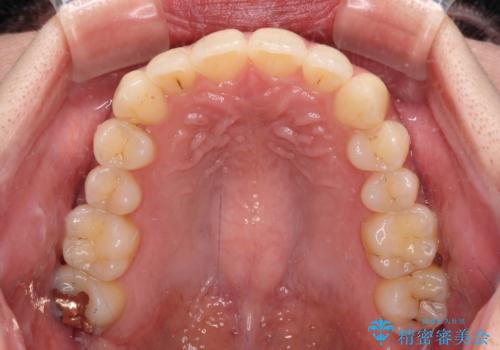

- 前歯のデコボコと強い咬みしめを気にして来院された患者様です。

インビザラインを用いて、前歯の叢生を解消するとともに、ディープバイトを改善していくこととしました。

海外へ転居する予定があったため、1日22時間以上の装着時間をしっかりと守っていただき、予定期間よりも早く、思っていた以上にきれいに仕上げることができました。